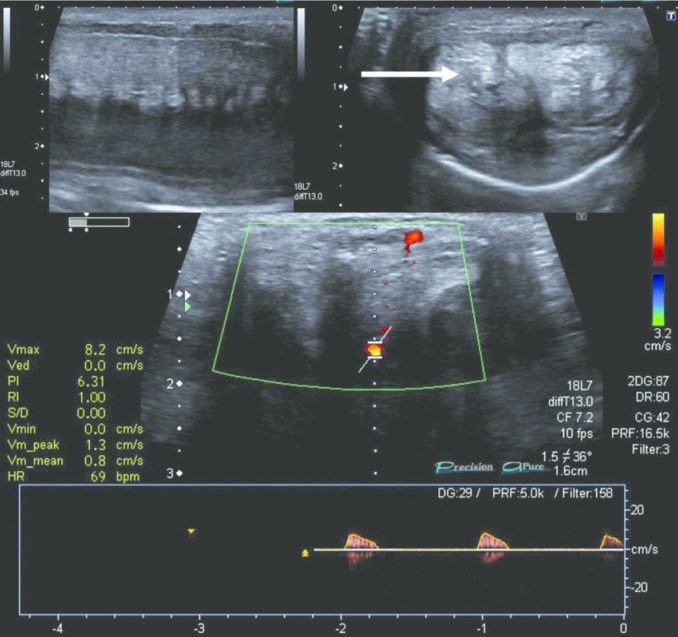

Badanie ultrasonograficzne Adama